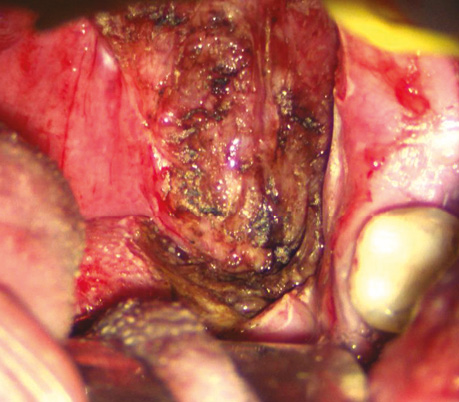

Пацієнт С., 56 років. Діагностовано плоскоклітинну карциному передньої піднебінної дужки з поширенням на корінь язика T2N0M0. Проведено трансоральну CO₂-лазерну резекцію бічної стінки ротоглотки та кореня язика доступом через сформоване «вікно» в ділянці дна ротової порожнини. На рис. 3–6 наведено етапи хірургічного втручання.

Рис. 3. Виконано розріз по серединній лінії дна ротової порожнини між під’язиковим мʼясцем у сагітальній площині

Рис. 4. Дисекція в напрямку до підпідборідного простору між черевцями підборідно-язикового та підборідно-під’язикового м’язів через щелепно-під’язиковий м’яз і між передніми черевцями двочеревцевого м’яза. Накладено лігатуру на кінчик язика, язик виведено через сформоване «вікно» дна ротової порожнини, що забезпечило візуалізацію кореня язика в анфас